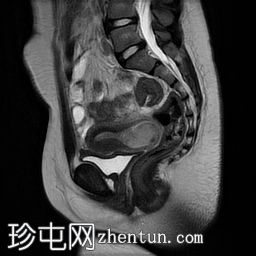

矢状面

T2

子宫体相对较小,发育良好。宫颈发育不全。

阴道整体不显影,远端可见一层细小的纤维组织,在轴向和矢状面T2加权序列上最为明显。

随后,子宫内膜和宫颈腔扩张,出现混合液体/血液降解信号(积血)。它诱发中至高T1信号,伴有依赖性低信号碎片,无病理性强化。

周围轻度盆腔积液,盆腔及附件脂肪平面模糊,信号相似,增强后强化明显。这些发现提示可能有渗漏液/血液积聚,并伴有腹膜反应。